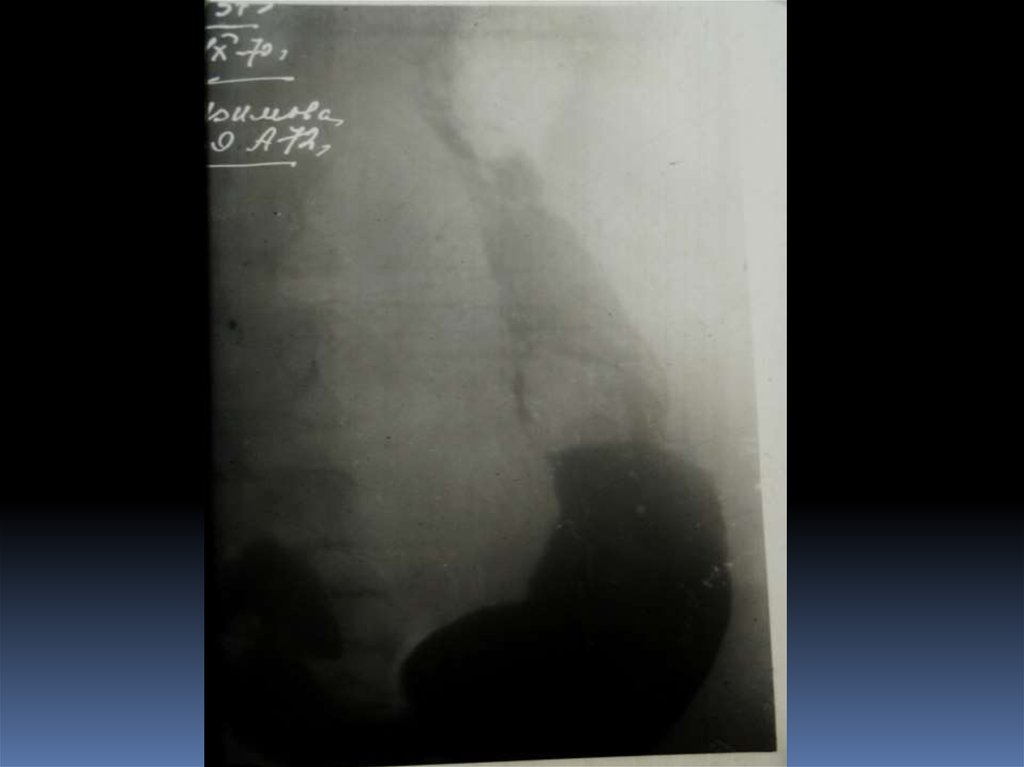

16. Рентгенодиагностика рака желудочно-кишечного тракта

Рентгенодиагностика

рака желудочнокишечного тракта

17. Классификация рака органов ЖКТ

1. Экзофитная форма:

2. Эндофитная форма:

узловая форма;

диффузноинфильтративная

форма;

полипоподобная

чашеподобная форма. инфильтративноязвенная.

3. СМЕШАННАЯ ФОРМА – 10-15%